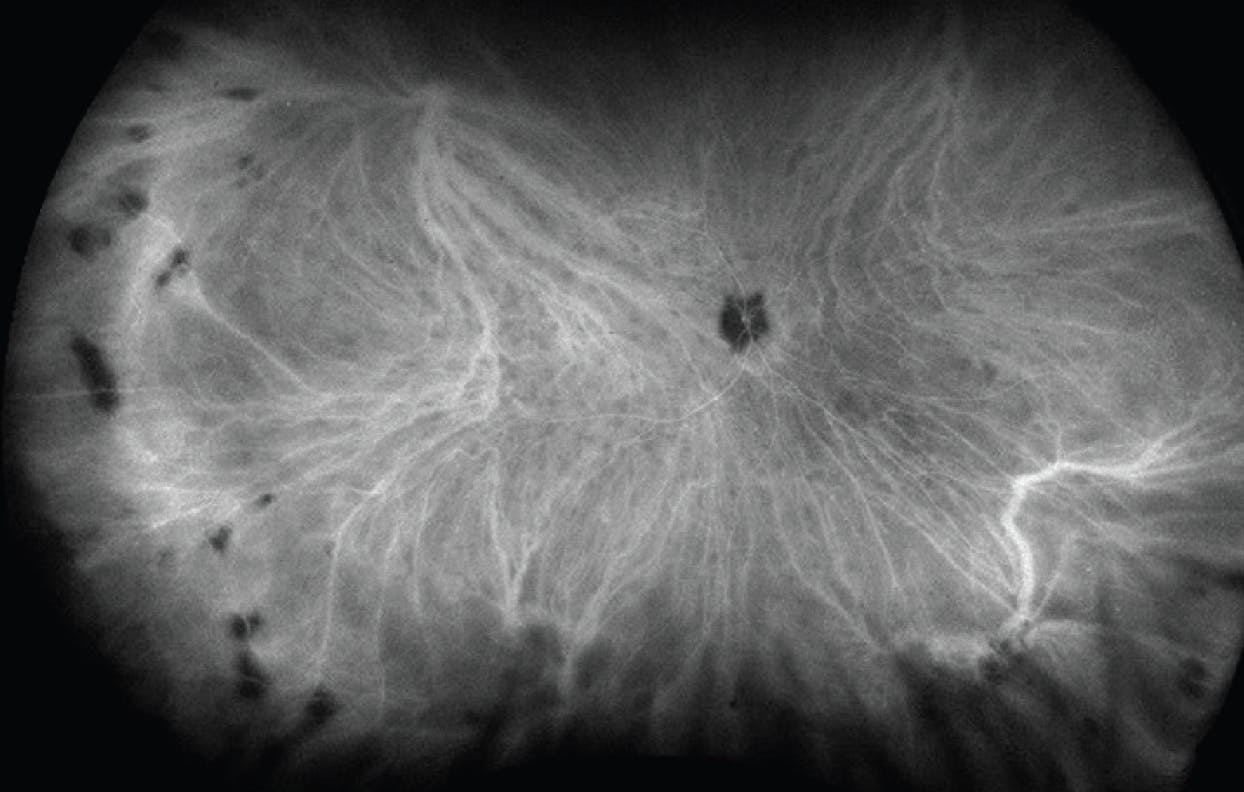

ICG angiography (ICGA) can highlight choroidal lesions that are not easily discernible on examination. Active choroidal inflammation presents as hypocyanescent spots on ICGA (Figure 5). Often, these areas correspond with lesions seen on FAF. UWF ICGA allows the capture of the full peripheral extent of these lesions, which proves particularly useful when monitoring for treatment response. Not all hypocyanescent lesions will resolve; those associated with scar or chorioretinal atrophy will remain, while active inflammatory granulomas often will resolve with treatment.

Figure 5. UWF ICGA of a patient with birdshot chorioretinopathy and multiple hypocyanescent lesions.